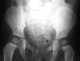

Fetal or neonatal liver calcification